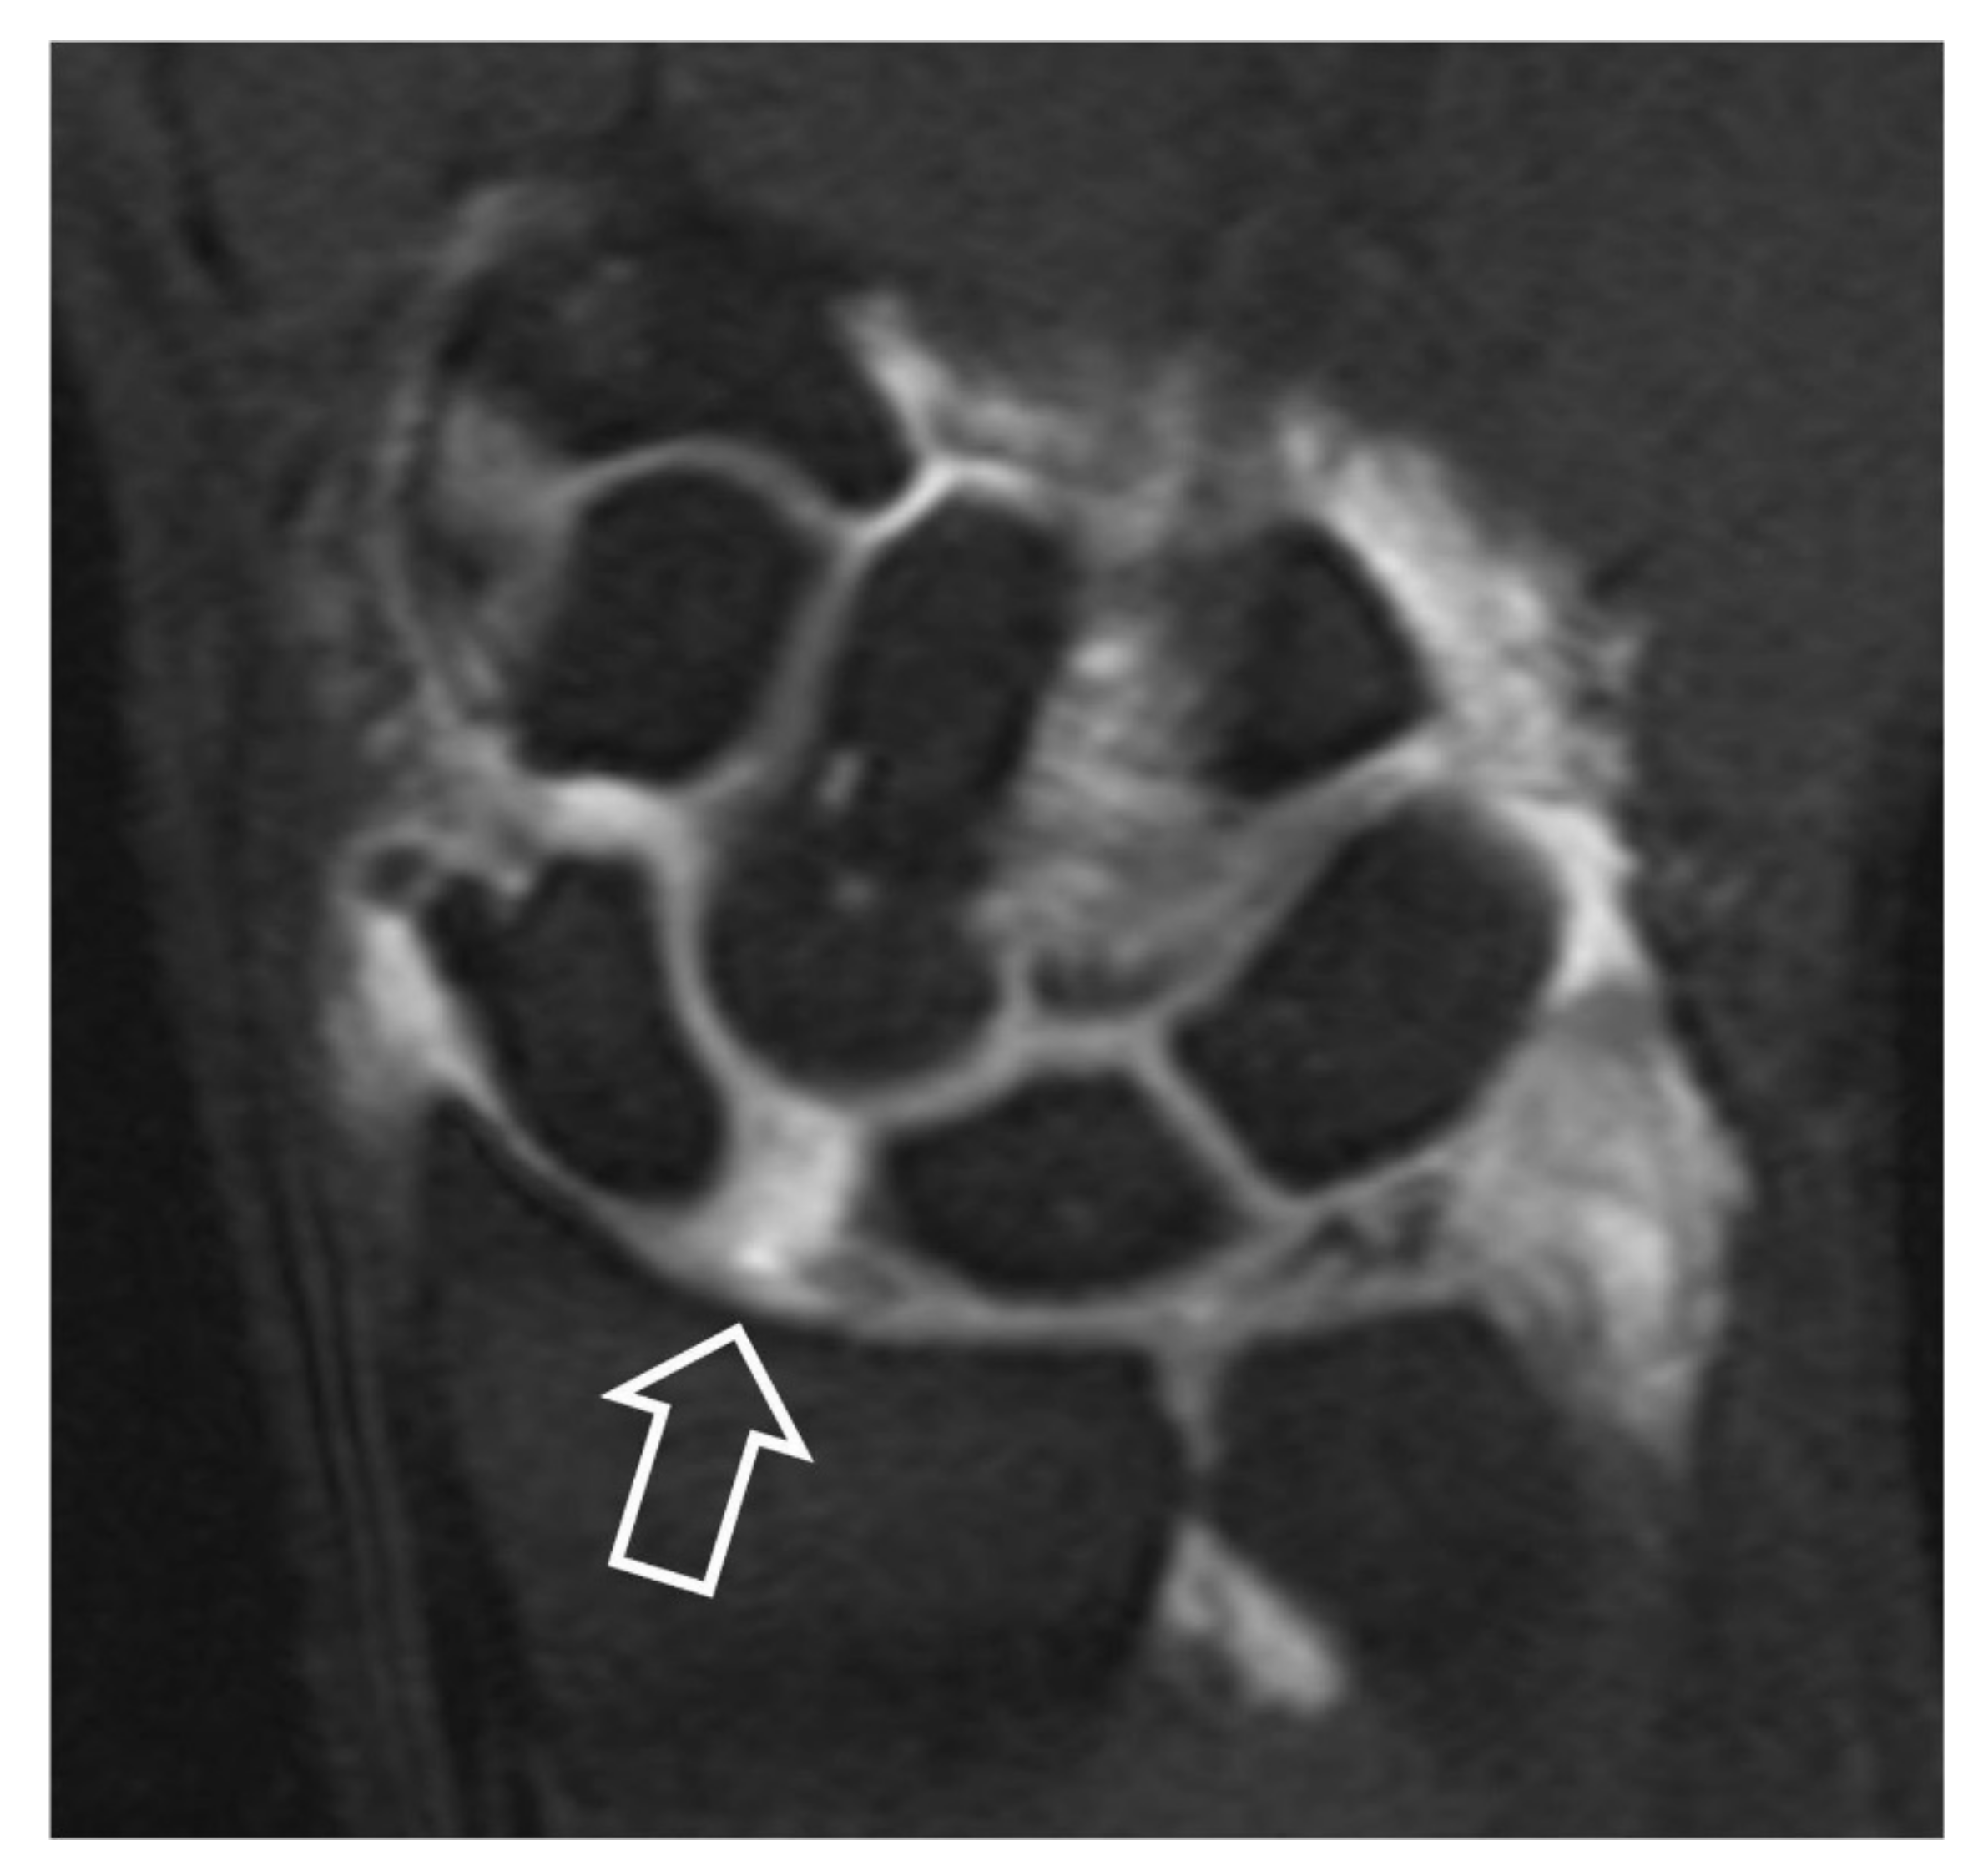

MRa can accurately assess the SLL disruption by depicting the absence of the ligament and the opacification of the midcarpal joints (Figure 12) [11]. Early changes of the articular cartilage in extreme detail concerning depth, height and thickness can be depicted (Figure 13) [12]. Axial images on MRI and MRa are more suitable for the estimation of wrist ligaments and sagittal images for the evaluation of scaphoid bone and DISI (Figure 14). Currently, MRI and MRa are the most widely preferred methods in diagnosing wrist pain [13]. Comparison of the various imaging modalities is shown in Table 3.

Figure 12.

Coronal fat suppressed T1w MR arthrographic image following a single injection in the radiocarpal joint. Scapholunate diastasis (open arrow) and opacification of the midcarpal joints suggest SLL disruption.

Figure 14.

DISI in a 66-year-old-male patient with SLAC wrist. (A) Sagittal MR arthrographic fat suppressed T1-w image showing the dorsal rotation of the lunate (arrows). (B) Coronal image showing a partial tear of the membranous part of the SLL. (C) Axial image showing the intact dorsal (arrowhead) and palmar (open arrow) parts of the SLL. The long arrow shows an air bubble injected with the contrast.